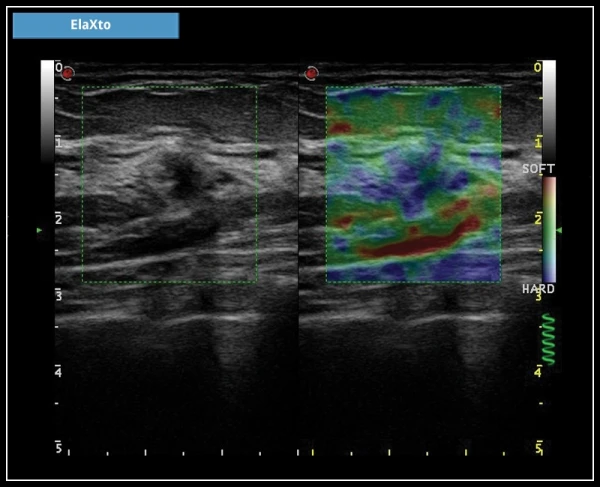

ElaXto: ElaXto – это неинвазивный метод, который помогает врачу оценить эластичность тканей. Различия в эластичности тканей обнаруживаются и визуализируются в реальном масштабе времени.